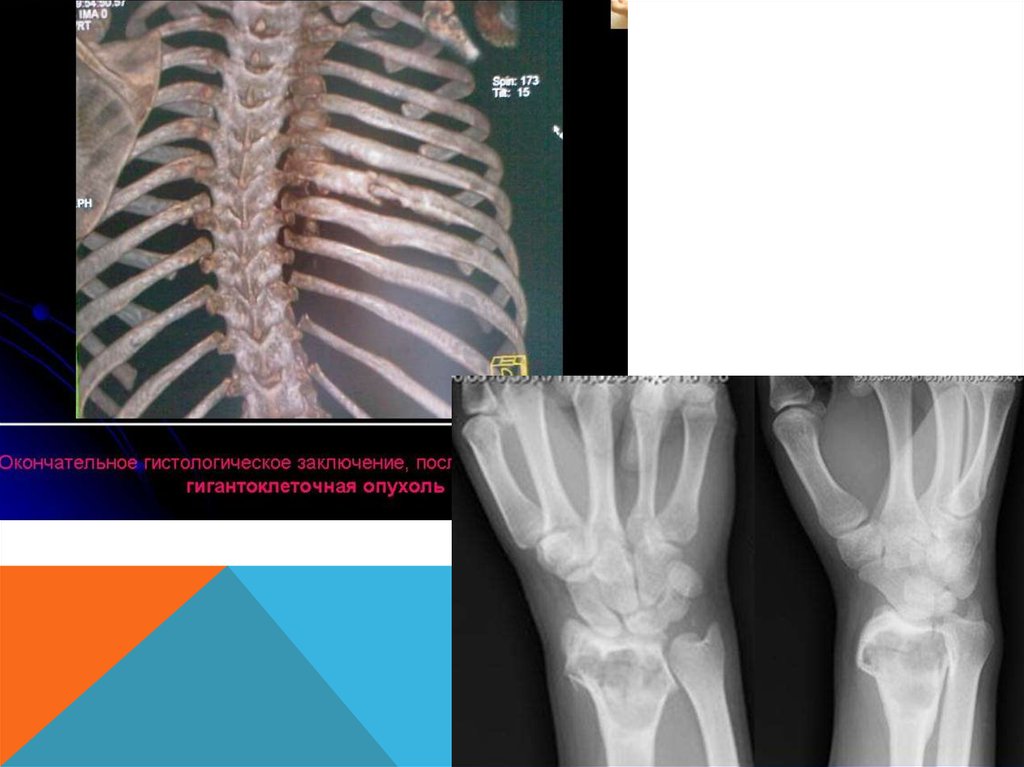

-Дистальный конец лучевой кости

умеренно «вздут»

-Корковый слой кости на этом уровне

значительно истончен, но всюду

сохранен; контуры его

крупноволнистые.

-Структура «вздутого» участка имеет

крупноячеистый рисунок.

Для постановки окончательного диагноза необходимо применить дополнительные методы пункцию и гистологическое исследование опухоли.

Пункцию опухоли следует проводить под местным обезболиванием толстой иглой в участке

наибольшего ее выпячивания в нижнем полюсе.

При остеобластокластоме получают пунктат буро-вишневого цвета, содержащий

гемосидерин, без кристаллов холестерина, или можно получить кровь